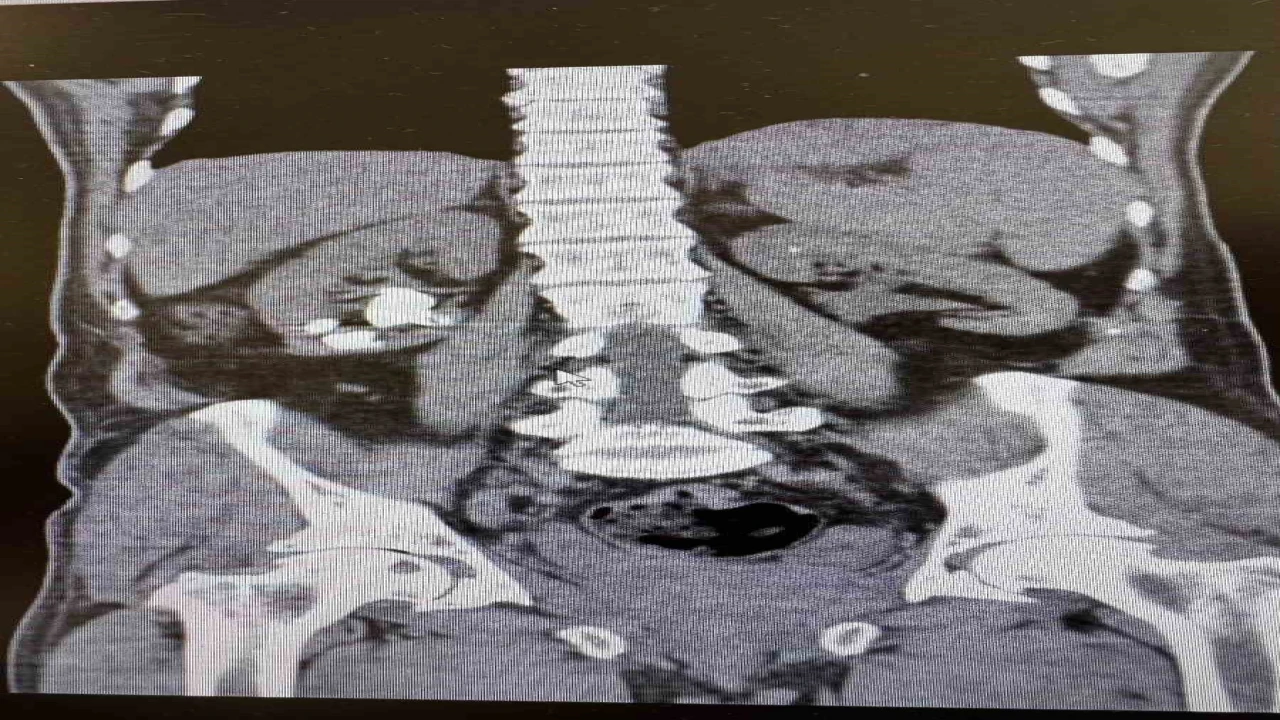

Üroloji Uzmanı Op. Dr. İlker Fatih Şahiner ve ekibince kapalı yöntemle (PNL) yapılan ameliyatlarda hastanın her iki böbreğindeki tekrarlayan sistin taşları temizlendi. Hastanın daha önce 10’un üzerinde böbrek taşı ameliyatı geçirdiği öğrenildi. Mayıs ayında yapılan ilk operasyonla sol böbrekteki taşlar alınırken, geçtiğimiz salı günü gerçekleştirilen ikinci operasyonla sağ böbrekteki taşlar da temizlendi.

Operasyonları gerçekleştiren Üroloji Uzmanı Op. Dr. İlker Fatih Şahiner, "Hastamızın her iki böbreğinde de tekrarlayan sistin taşları mevcuttu. Mayıs ayında sol böbreğine PNL yaparak taşsızlık sağlamıştık. Dün de sağ böbreğine PNL ameliyatını yaparak taşsızlık sağladık. Hastamızın genel durumu iyi, tedavisi servisimizde devam ediyor" dedi.